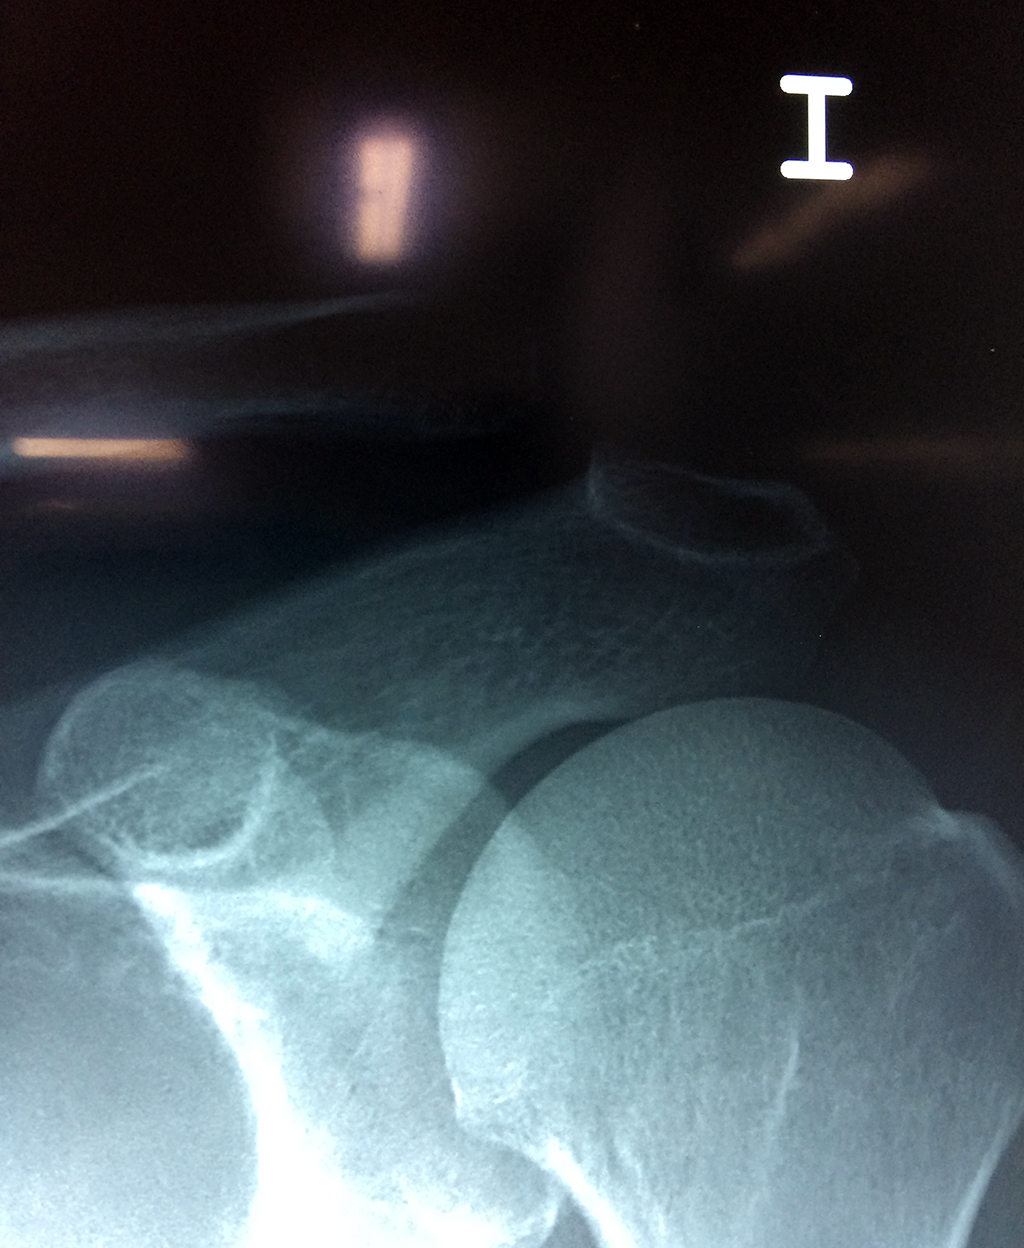

Clavícula

La clavícula es un hueso largo, con forma de "S" itálica, situado en la parte anterosuperior del tórax. Junto con la escápula forman la cintura escapular. Se puede palpar por toda su longitud y se extiende del esternón al acromion de la escápula, siguiendo una dirección oblicua lateral y posterior.

Se considera el único medio de unión entre el miembro superior y el tórax. A pesar de su aspecto, similar al de un hueso largo, posee una estructura semejante a la de un hueso plano, ya que carece de epífisis y de diáfisis, lo que la harían entrar dentro de la clasificación de hueso largo. Carece de un canal medular propiamente dicho.